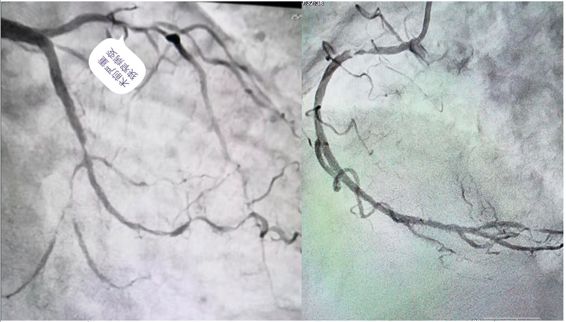

刘大娘今年70岁,家住秀山县。因“上腹疼痛1月余,腹胀纳差6天”到重医大附二院秀山分院消化内科住院,伴有糖尿病、高血压病史多年。入院后查心电图及肌钙蛋白异常,经过心内科医生会诊后考虑为急性非ST段抬高型心肌梗死,立即转入心内科治疗,紧急行冠脉造影提示冠脉三支病变:前降支近段至中段弥漫性病变伴严重钙化,狭窄最重达90%;回旋支中远段弥漫性病变,狭窄最重达85%;右冠最重病变狭窄程度达95%。

由于病情十分危重,经过规范的冠心病药物治疗,胸痛症状仍没有明显好转;病变处钙化非常严重,于前降支病变处行球囊扩张时,球囊无法扩张。就在刘大娘及家属处于绝望边际之时,在秀山分院挂职副院长的重医大附二院心血管内科陈运清教授了解情况后,多次组织心内科医生讨论病情、制定治疗方案,并反复与大娘及家属沟通,最后终于打消顾虑,一致决定择期行血管内超声指导下(IVUS)的冠脉旋磨术和冠脉介入治疗。

没有金刚钻,不揽瓷器活。”7月19日,手术由陈运清教授主刀,首先进行了IVUS检查,提示冠脉病变呈360°钙化;随后,对病变处成功进行了冠脉内旋磨术和支架植入术,并用IVUS复查证实支架覆盖全部病变且贴壁良好,完成血运重建。术后,大娘病情好转,疼痛症状明显消失。26日,阳光普照,当陈教授来到心血管内科A区5号病床时,刘大娘和家人们正在收拾东西准备办理出院。陈教授悬着的心终于落下来了,走到大娘身旁关切地询问病情时,大娘一把握住他的双手,激动地说:陈教授,多亏了您治好了我的病,现在胸口不痛了,胃口好了,吃啥都香了!没想到在这偏远山区,咱老百姓也可以找到大医院的专家来治病!